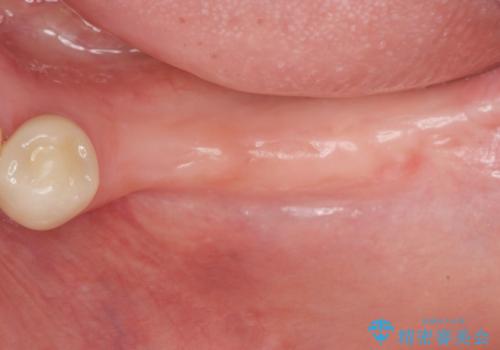

インプラント治療を行ったことでしっかりと噛めるようになり、また清掃性の高い環境を整備したことで長期的な予後も期待することができます。